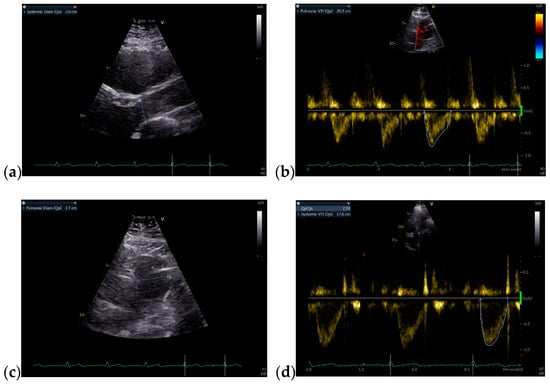

A 36-year-old non-smoker male patient, without cardiological follow-up and no cardio-active medication at home, presented with dyspnea, mild effort intolerance, and headache. Physical examination revealed peripheral cyanosis, body mass index (BMI) = 27.68 kg/m2, blood pressure (BP) = 115/70 mmHg, heart rate (HR) = 75 bpm, and unremarkable cardiac and pulmonary auscultation. The electrocardiogram showed sinus rhythm, HR = 75 bpm, rSR’ pattern in precordial leads V1 or V2 (Figure 1a). The chest radiography revealed a normal heart size with hilar bilateral enlargement and increased vascular density in the upper half of the hilum (Figure 1b).

Figure 1.

(a) 12-lead ECG revealed sinus rhythm and rSR’ pattern in precordial leads V1 or V2; (b) Postero-anterior chest view radiography showed hilar bilateral enlargement and increased vascular density in the upper half of the hilum. Abbreviations: ECG—electrocardiogram.

Under local anesthesia, the implantation of a single-chamber VVI mode cardiac pacemaker was carried out. The programmed HR was 55 bpm. The postprocedural ECG showed intermittent efficient ventricular paced rhythm, with HR = 57 bpm (Figure 10a). The chest radiography revealed a single-chamber pacemaker and increased vascular density in the upper half of the hilum (Figure 10b).

Figure 10.

(a) 12-lead postprocedural ECG showed intermittent efficient ventricular paced rhythm; (b) Postero-anterior chest view radiography highlighting the presence of a single-chamber pacemaker and increased vascular density in the upper half of the hilum. Abbreviations: ECG—electrocardiogram.